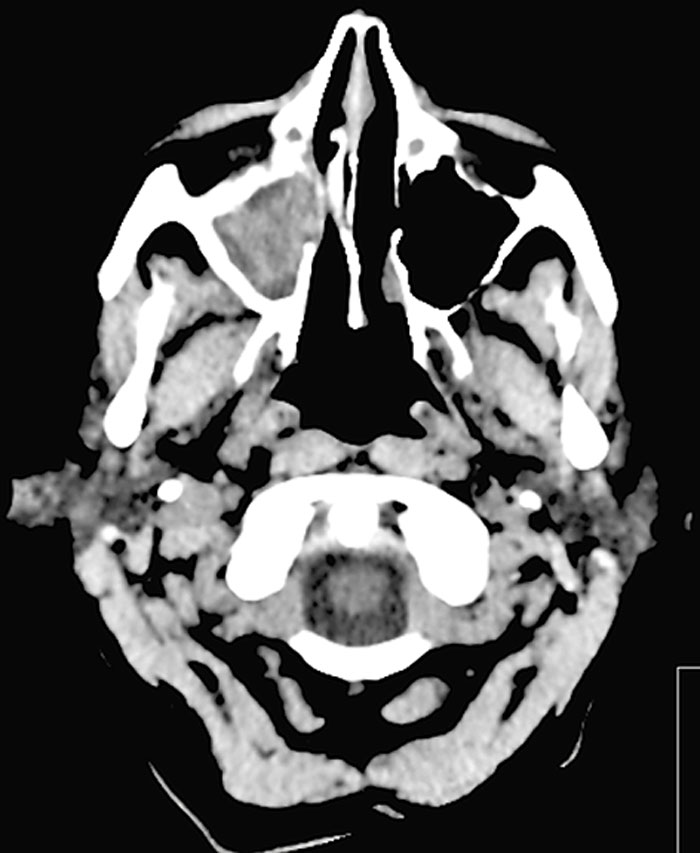

Fallrapport 3 [59] (Fakta 1) rör en 46-årig man som sökte med svår huggande smärta sedan fem månader. Huvudvärken kom i attacker och satt bakom vänster orbita. Klinisk undersökning/laboratorieprov var u a. Patienten uppfyllde kriterierna för klusterhuvudvärk, och terapi med sumatriptan i tablett- och injektionsform sattes in tillsammans med verapamil som förebyggande medel. Han svarade på akut­be­handlingen (injektion sumatriptan) med minskning av huvudvärken inom 20 minuter, och attackerna minskade betydligt i frekvens inom en vecka. På grund av relativt sent debuterande klusterhuvudvärk beställdes en poliklinisk MR. Undersökningen visade en hypofystumör (Figur 3). Vidare utredning visade prolaktinom. Specifik terapi sattes in, och huvudvärken förbättrades och försvann sedan helt. Terapin mot klusterhuvudvärken kunde sättas ut, och patienten har inte upplevt några fler huvudvärks­attacker vid uppföljningen efter flera år.

Figur 3. MR hjärna (sella), T1 sagittalt medellinjesnitt, visar en hypofystumör/prolaktinom (pil).